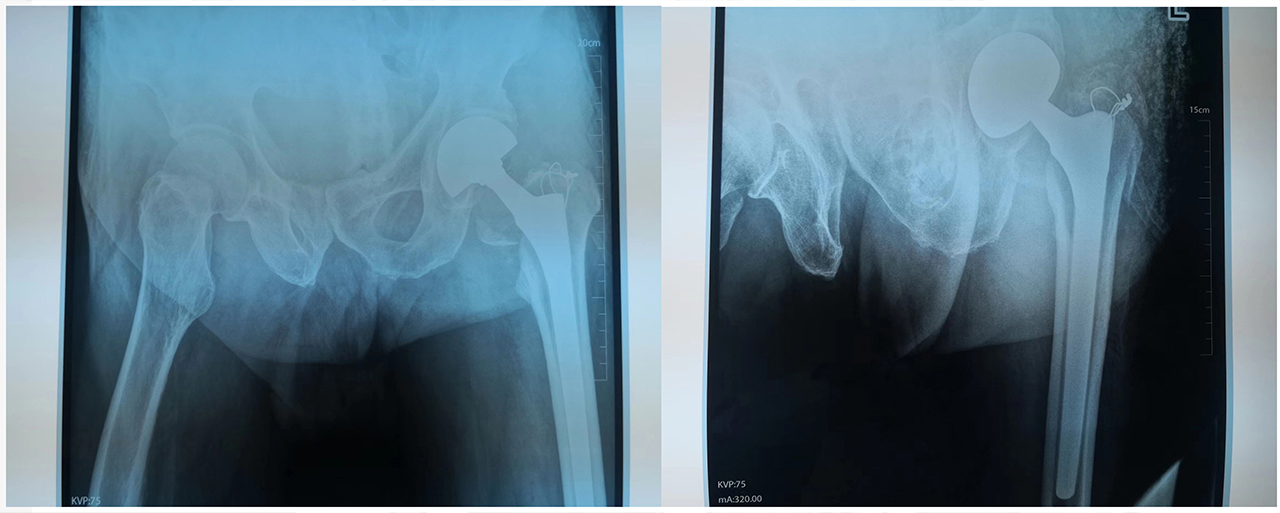

找庞润明主任治疗。诊断为:左股骨粗隆间骨折。 图说:患者术前DR片 入院后给予详细查体,经心电图室、CT室、化验室等各科室的共同配合下,迅速完善各项术前检查。通过庞润明主任及主管医生认真评估,分析了可能遇到的各种困难,决定老人可以行手术治疗。 图说:患者术中DR片 在手术室人员的共同配合下,手术顺利完成,术后髋关节正侧位DR 片,手术非常成功。 图说:患者术后DR片 股骨头置换术后的护理同样非常的重要,护士对大爷及家属进行了健康宣教,帮助患者做了如何坐立、上下床的练习,最终在我们医护人员的共同努力下,患者下地走路了,露出了满意的笑容。 图说:在医护人员的指导下患者下地走路 通过我们全体医护人员的精心照顾,细心的呵护,点点滴滴的付出,给患者鼓足了勇气,更加有信心面对病痛的折磨,战胜了病魔的纠缠。健康所系,性命相托!我们骨科全体医护人员竭诚为您服务!